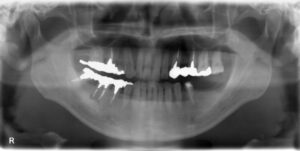

下顎大臼歯2本欠損症例

BEFORE AFTER 42歳女性/下2本/インプラント埋込手術 【治療内容】 左下第二大臼歯の歯根の部分の虫歯が進ん…